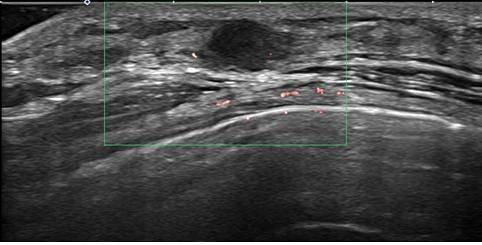

유방촬영술은 유방암 검진의 가장 기초적인 검사 방법으로, 미세 석회화를 가장 잘 검사하는 방법이다. 유방암과 연관된 미세 석회화는 초음파나 MRI에서 보이지 않는 경우가 있어 유방촬영술 검진은 반드시 받아야 한다. 한국인은 유방 조직이 치밀한 치밀 유방을 가진 경우가 많은데 이것도 유방암의 발병 원인 중 하나다. 치밀 유방인 경우에는 유방 초음파가 도움이 된다. 고위험군이라면 필요시 MRI 검사를 시행하게 되며 영상학적 검사 이후 필요하다면 조직 검사를 통해 유방암을 진단한다.